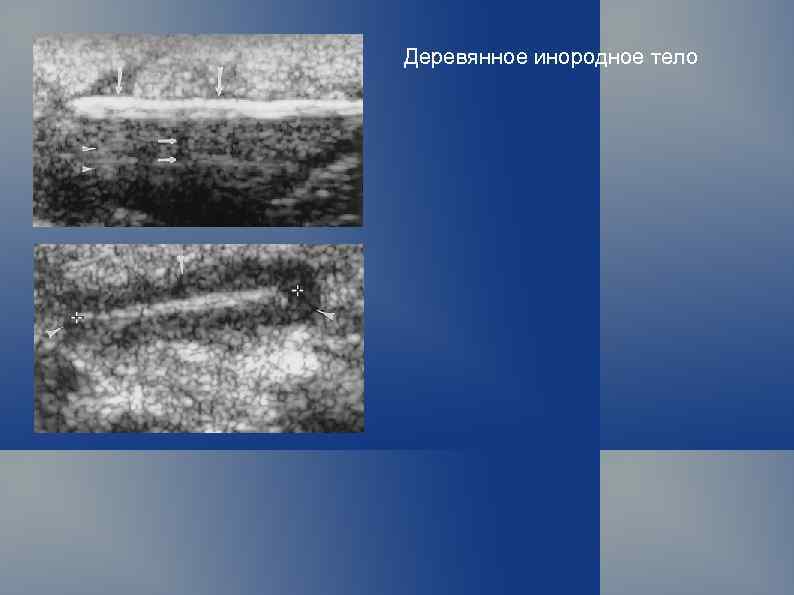

Инородные тела: деревянные щепки

Деревянное инородное тело